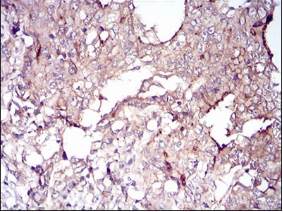

VIL1 Mouse Monoclonal antibody[5E3B2]

IHC    1/200 - 1/1000